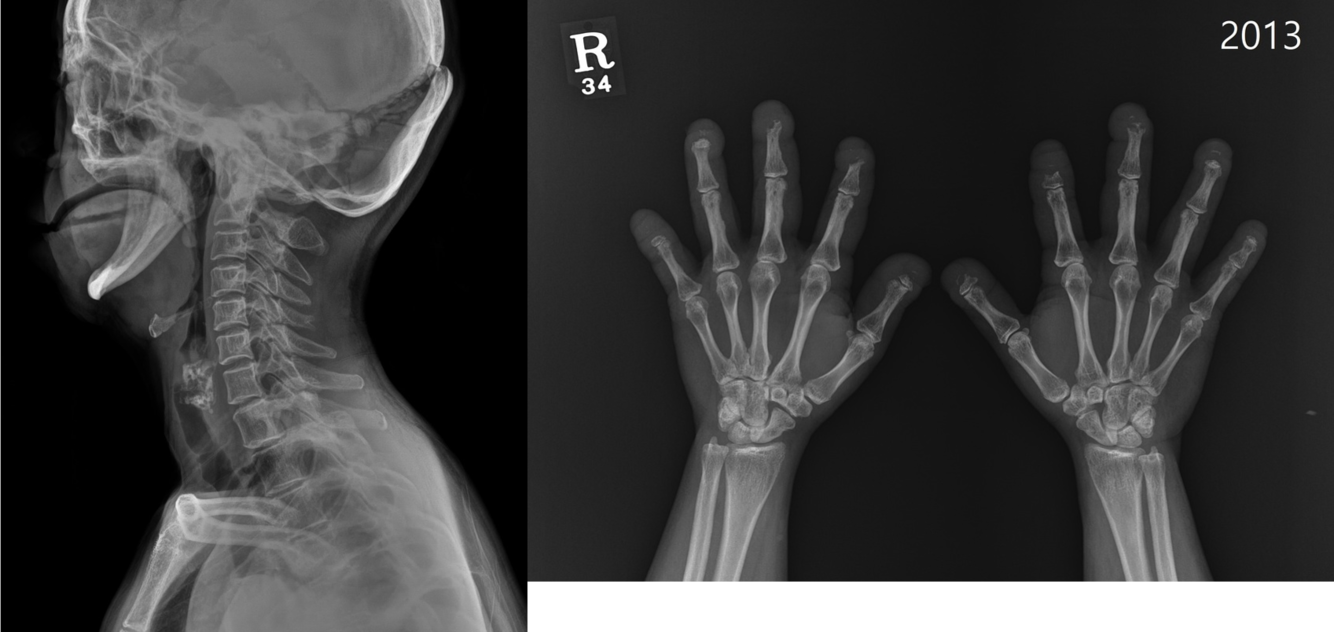

deforming non-erosive arthropathy characterized by ulnar deviation of the second to fifth fingers with metacarpophalangeal joint subluxation.

Jaccoud arthropathy

% of pts with SLE with joint involvement

90% of SLE pts have joint involvement

Reducible subluxations of the MCPs and PIPs

SLE

MCP subluxation with ulnar deviation. No erosions. Related to ligamentous laxity

Jaccoud arthropathy (think SLE)

historically described as being secondary to recurrent rheumatic fever (now associated with SLE) deforming non-erosive arthropathy characterized by ulnar deviation of the second to fifth fingers with metacarpophalangeal joint subluxation.